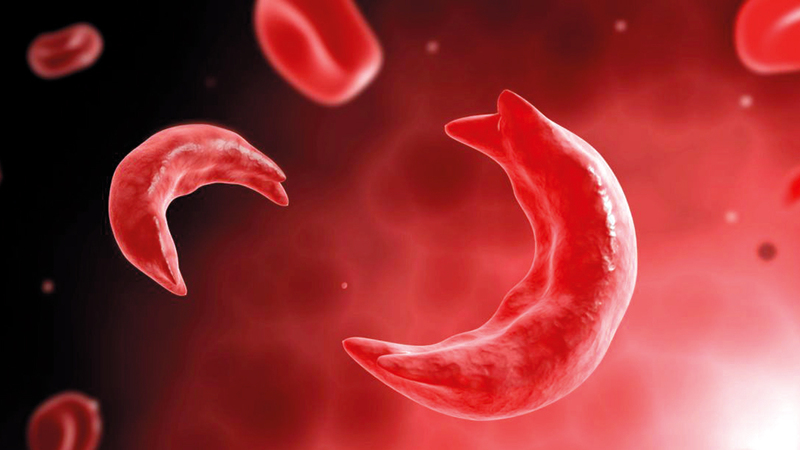

Etavopivat is the first in a new class of drugs to successfully meet both co-primary end-points in the phase 3 HIBISCUS trial, substantially reducing vaso-occlusive crisis events and improving haemoglobin response in sickle cell disease

Novo Nordisk today announced the topline results from HIBISCUS, a pivotal phase 3 trial of once-daily oral etavopivat in adults and adolescents with sickle cell disease (SCD). The results showed that etavopivat successfully met both co-primary endpoints, demonstrating superior reduction in vaso-occlusive crises (VOCs) and superior improvement in haemoglobin (Hb) re-sponse compared to placebo.

Etavopivat is an oral, once-daily, pyruvate kinase-R (PKR) activator being developed to treat SCD, a seriously debilitating, life-threatening and life-shortening disease that impacts around 8 mil-lion people worldwide.

In the trial1, people treated with etavopivat demonstrated a superior reduction in the annual-ised rate of VOCs of 27% compared to placebo. The time to first VOC was significantly prolonged with etavopivat, with a median time to first VOC of 38.4 weeks versus 20.9 weeks for placebo.

In addition, etavopivat demonstrated a superior increase in the proportion of people achieving a Hb response greater than 1g/dL at week 24 of 48.7% compared to 7.2% with placebo, corre-sponding to an adjusted rate difference of 41.2%1. Further, as an exploratory analysis, etavopivat significantly reduced the risk of blood transfusion.